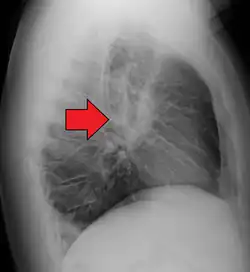

-

Hilar adenopathy especially on the person's left (AP CXR)

Hilar adenopathy especially on the person's left (lateral CXR)

Hilar adenopathy especially on the person's left (coronal CT)

Hilar adenopathy especially on the person's left (transverse CT)

Chest radiograph changes are divided into four stages:[104]

- bihilar lymphadenopathy

- bihilar lymphadenopathy and reticulonodular infiltrates

- bilateral pulmonary infiltrates

- fibrocystic sarcoidosis typically with upward hilar retraction, cystic and bullous changes

Although people with stage 1 radiographs tend to have the acute or subacute, reversible form of the disease, those with stages 2 and 3 often have the chronic, progressive disease; these patterns do not represent consecutive "stages" of sarcoidosis. Thus, except for epidemiologic purposes, this categorization is mostly of historic interest.[28]